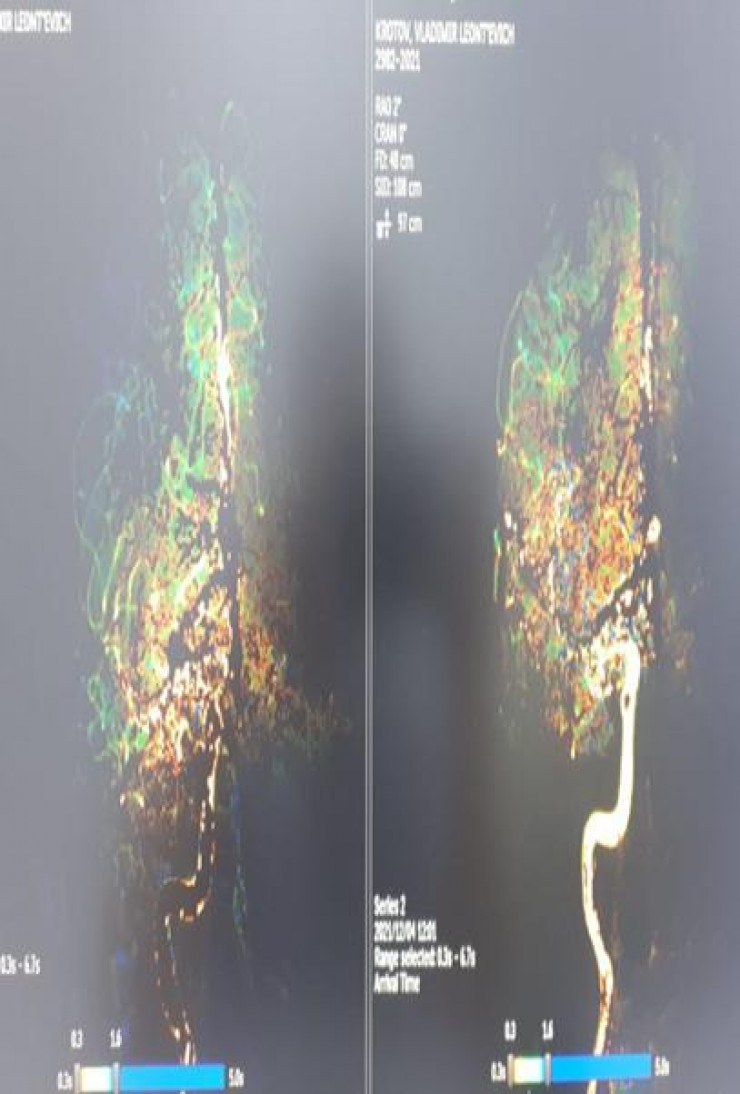

На момент прибытия пациента в больницу он находился в инсультном состоянии более трех часов. Врачи решили провести ему экстренную операцию с помощью аппарата ангиографии, то есть без разреза ножом.

Операцию выполнили главный врач больницы и главный внештатный рентгенхирург города, врач высшей категории Асхар Рахматалиев и рентгенхирург больницы Нуржан Карабаев. Она длилась два часа.

"Сделали тромбоэктомию через ангиографический аппарат. Пациент чувствует себя очень хорошо, самостоятельно стоит, отвечает на вопросы. Инсультный центр городской больницы № 2 работает на трех уровнях. Если пациенты поступают в больницу в течение 4-6 часов от начала инсульта, мы успеваем оказать качественную специализированную технологическую медицинскую помощь. То есть в таком случае у пациента есть шанс выжить", - говорит заведующий отделением Руслан Исабекулы.